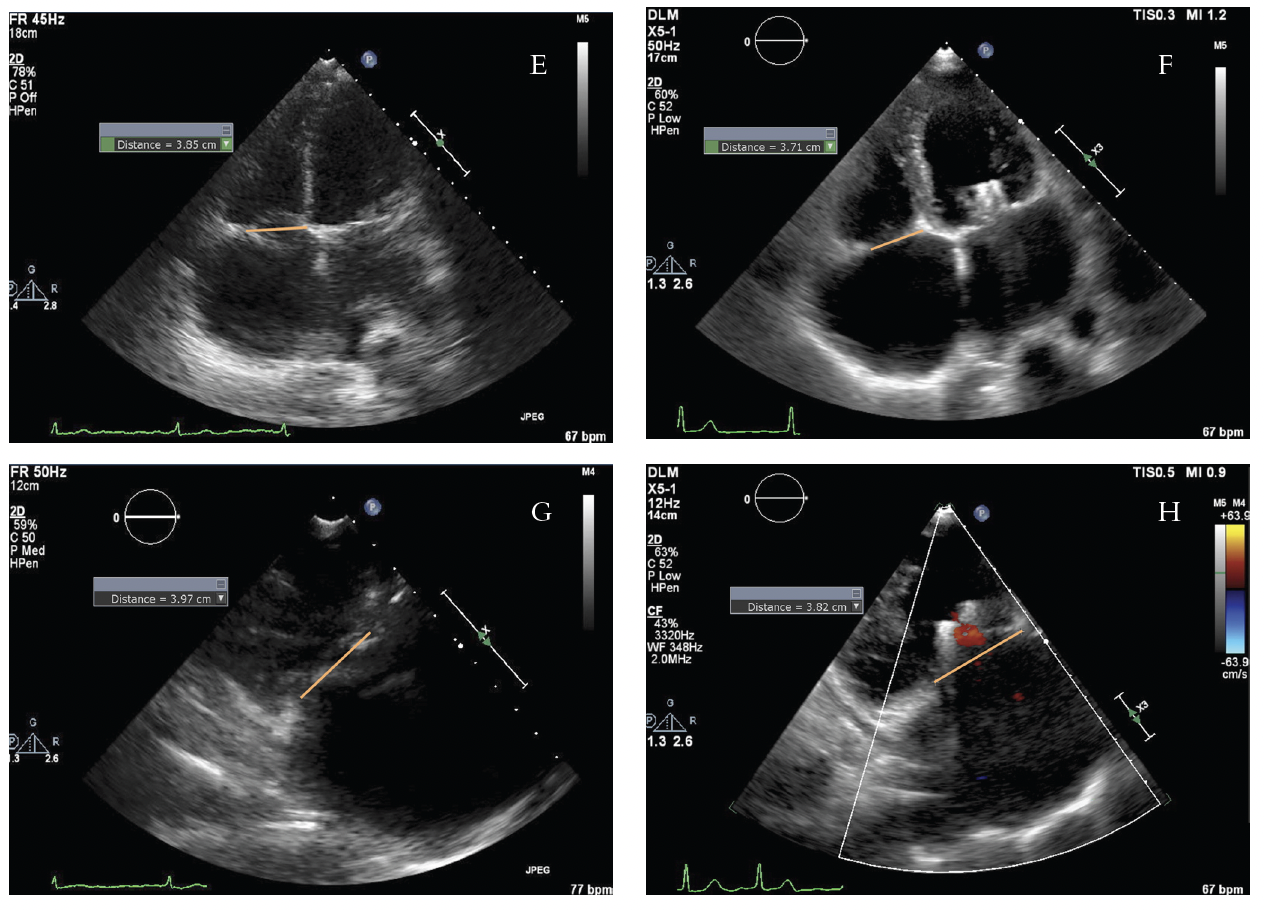

At the end of the procedure, there was almost full closure of the anterior-septal commissure; thus, bicuspidization of the tricuspid valve was achieved (Figure 6). There was still significant severe tricuspid regurgitation with systolic flow reversal in the hepatic veins. However, there was a reduction in the vena contracta from 1.68 cm to 0.94 cm in the four-chamber TEE view and from 2.1 cm to 0.7 cm in the right ventricular inflow TEE view. There was also a decrease in tricuspid valve area from 8.9 cm2 to 3.77 cm2. In addition, a reduction in tricuspid valve dimensions was seen.